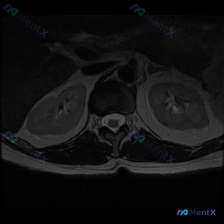

用户提供一张腹部MRI轴位T2加权图像,问题是:判断这张影像上是否存在椎间盘病变。

- 图像质量:对比度良好,能清晰显示腹膜后结构,无明显运动伪影

- 解剖定位:这是上腹部/腹膜后水平的切面,主要显示双肾、腰椎椎体层面椎管、腹主动脉和周围腹膜后软组织

- 双肾形态、大小、信号都正常,没有明显肿块或弥漫性异常

- 椎体、背部肌肉信号正常,椎管内脑脊液信号符合T2WI表现

- 腹主动脉流空信号正常,走行正常

- 肾周、主动脉周围腹膜后间隙没有异常渗出、肿块或者肿大淋巴结

- 解剖层次清晰,肾筋膜走行自然,没有占位效应

客观结论:这一断层面显示的是正常腹膜后/肾区解剖结构,没有发现明确的病理性异常。

这里其实有一个很关键的矛盾:用户要找椎间盘病变,但这张影像本身就没清晰显示腰椎间盘结构——评估椎间盘通常需要矢状位或者更低位置的轴位图像,当前层面根本没覆盖到需要评估的目标结构。